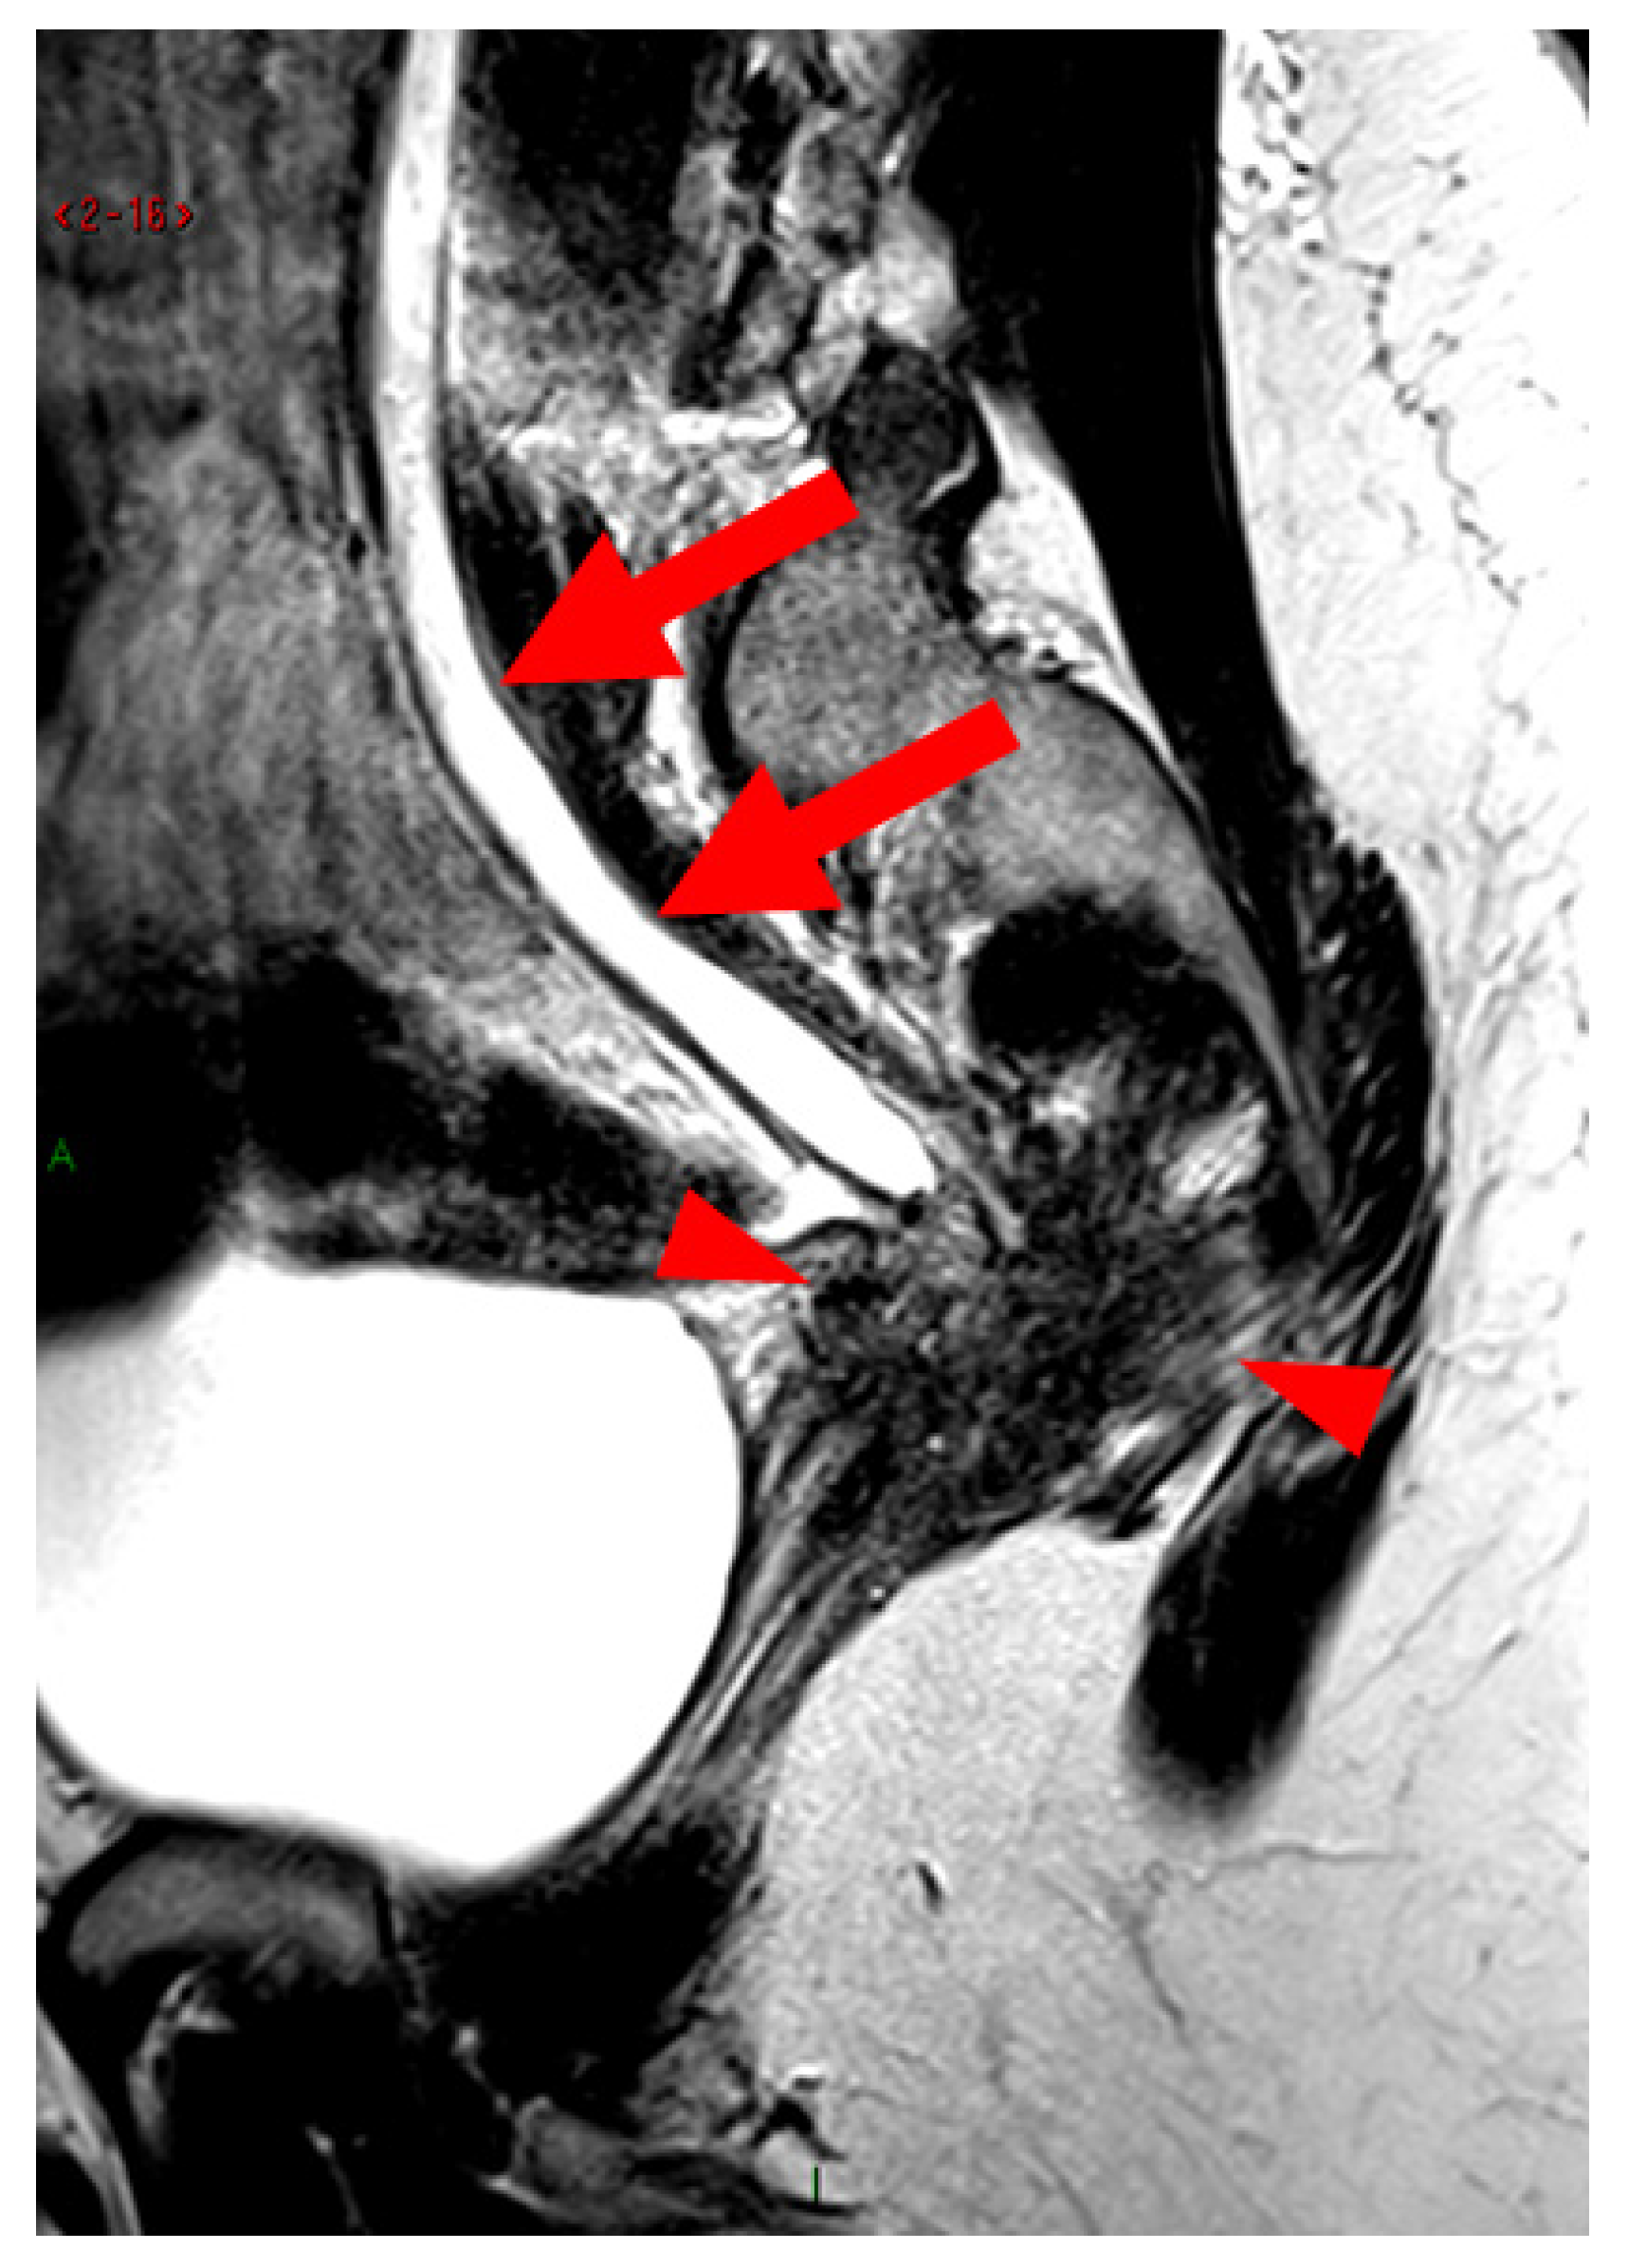

Figure 10. Pelvic MRI scan of a patient with HTD type 6 USLs. Sagittal T2WI demonstrates nodulospicular infiltration of the sacro-recto-genital septum, with the endometriotic lesion delineating the structure of the inferior hypogastric plexus (arrowheads). Note that the lesion also involves the distal ureter, causing upstream ureteral dilation (arrows).

A type 6 USL is associated with adjacent pelvic “visceral” involvement in a broad sense. It most commonly affects the digestive tract (Figure 8 and Figure 9), with the rectum and rectosigmoid junction wall thickening: in this case, the lesion often appears as a “medallion-shaped” protrusion into the lumen. Less frequently, the urinary tract is affected (Figure 9 and Figure 10), involving the muscular layer of the bladder or even the distal ureter at the level of the common iliac artery, with stenosis potentially leading to upstream hydronephrosis. More rarely, as USLs are also close to nearby pelvic nerve structures (Figure 11), contiguous involvement of the inferior hypogastric plexus located in the sacro-recto-genital septum (a.k.a. Delbet sagittal fascia) beneath the distal two-thirds of the USL, or exceptional involvement of the sciatic nerve adjacent to the pelvic wall, is possible (Figure 12, Figure 13 and Figure 14).